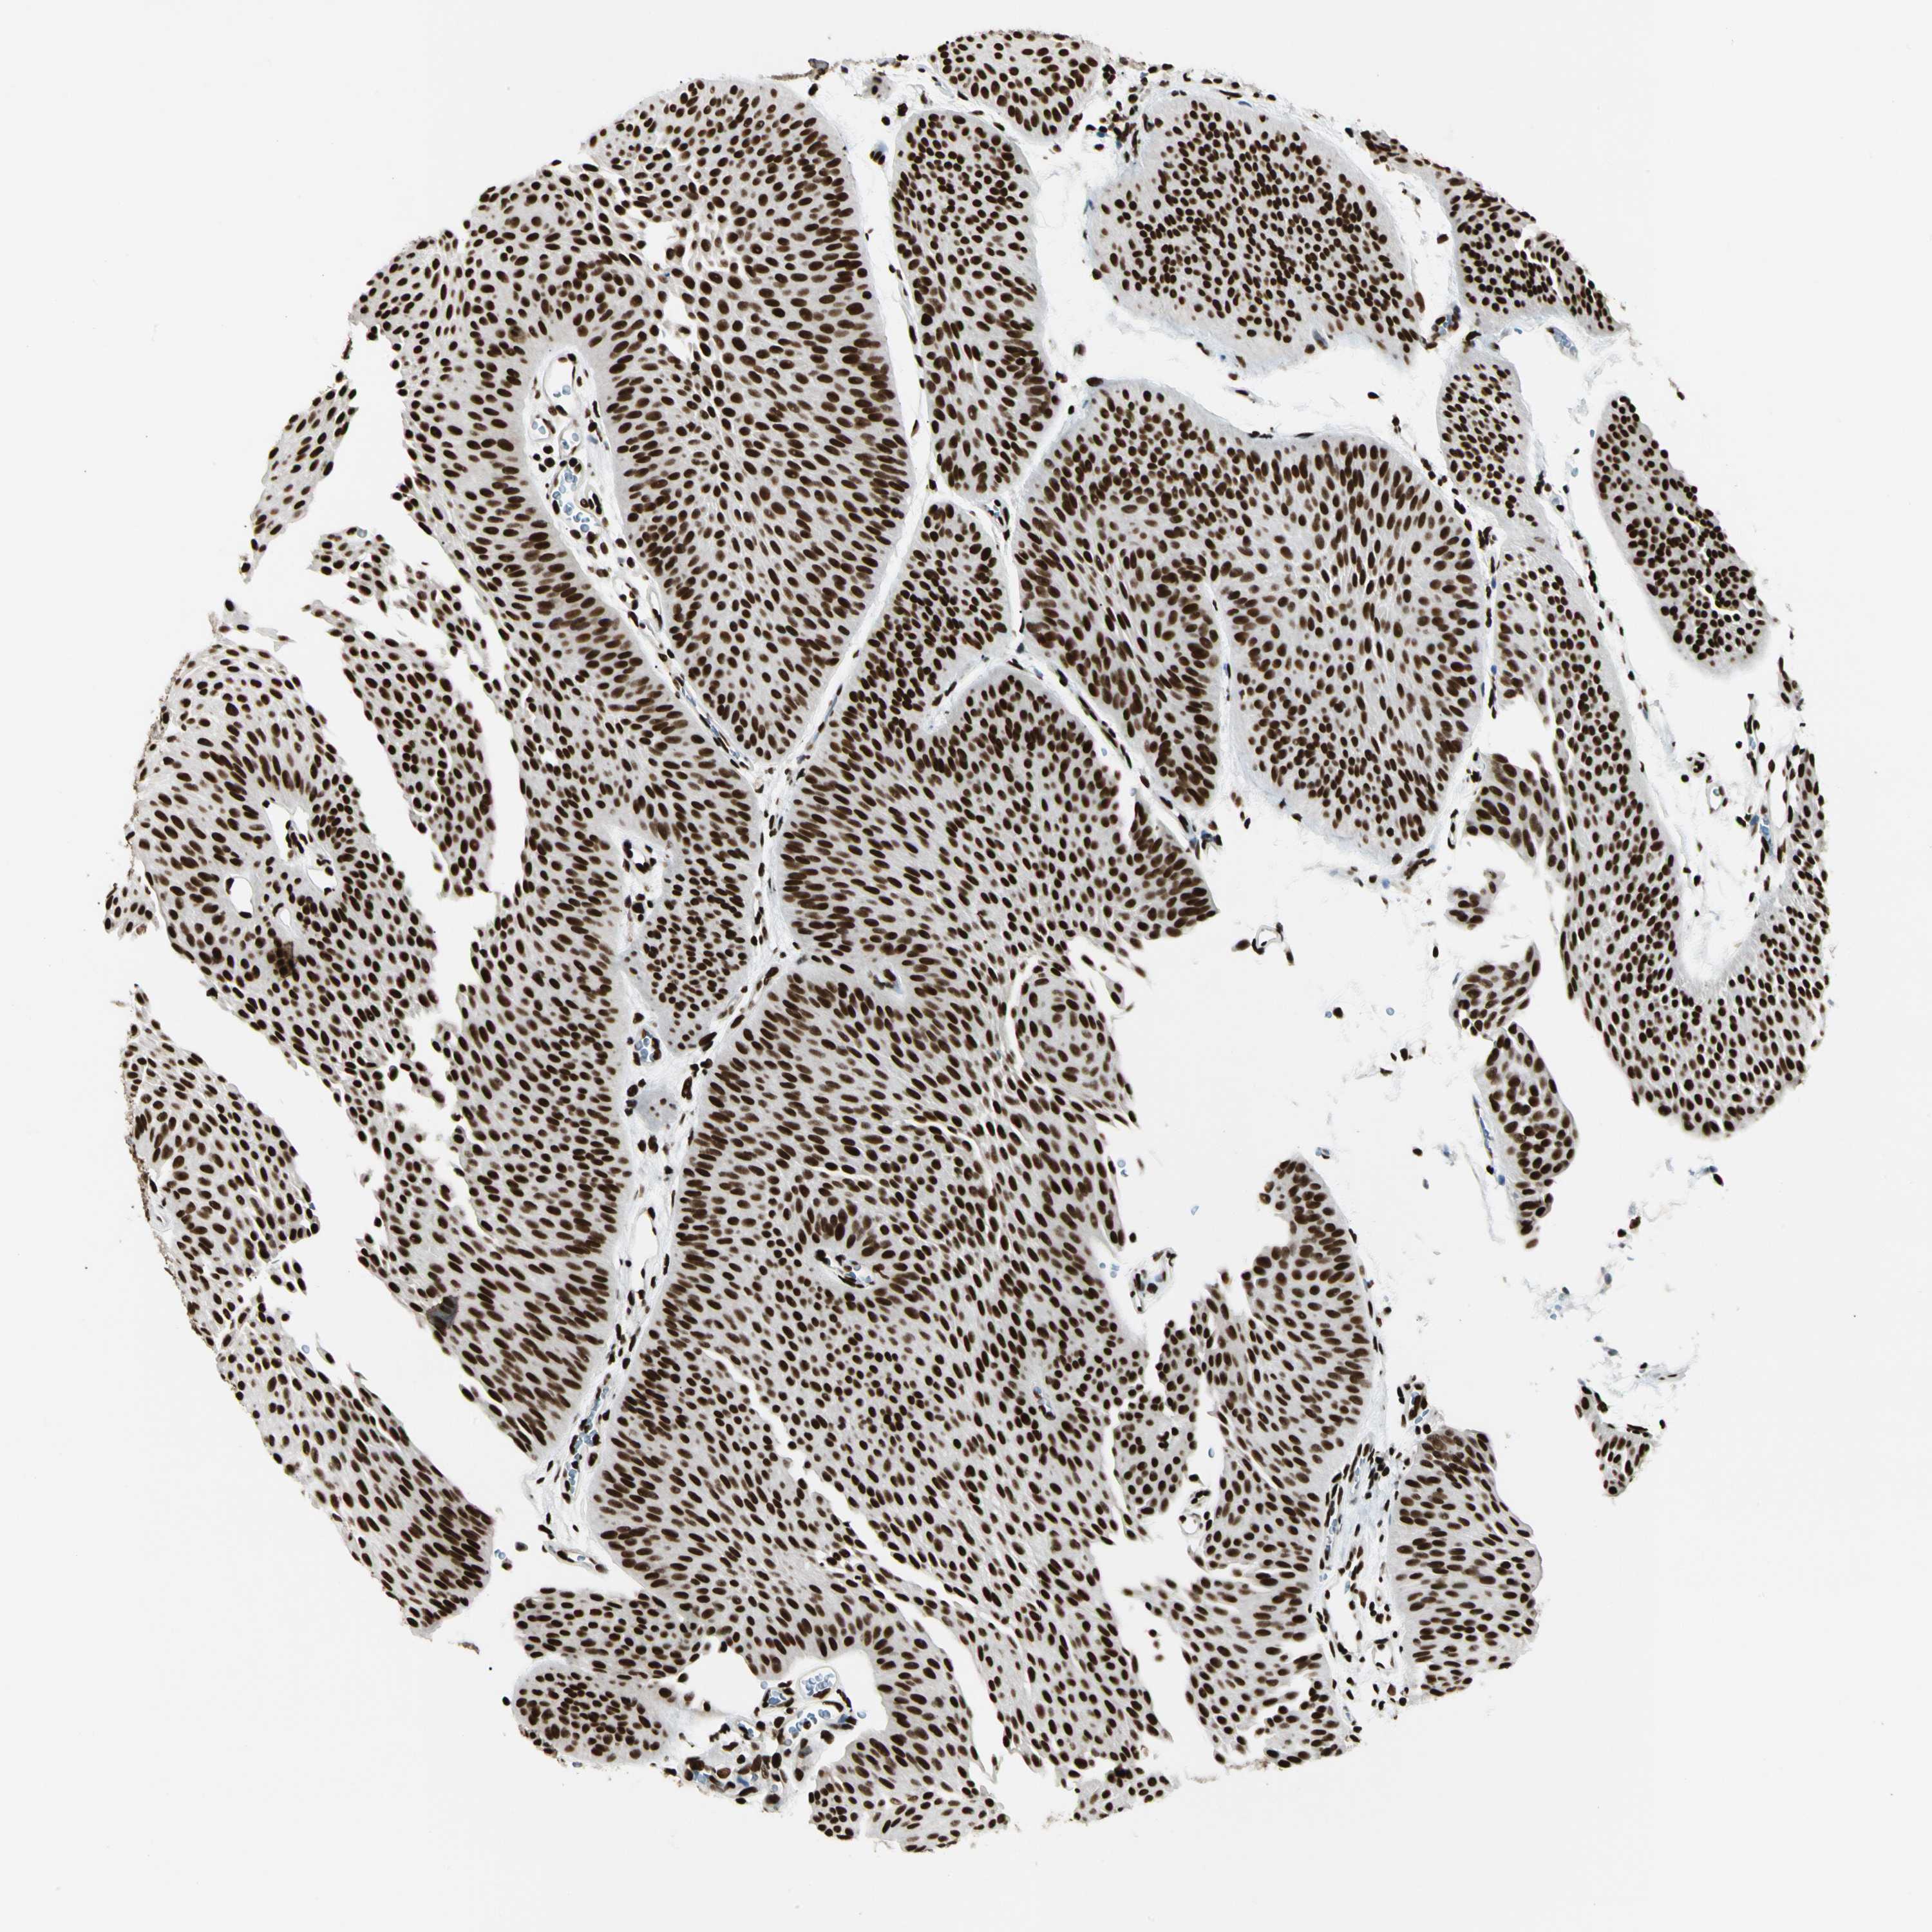

UROTHELIAL CANCER - Protein expressioni

A mouse-over function shows sample information and annotation data. Click on an image to view it in a full screen mode. Samples can be filtered based on level of antibody staining by selecting one or several of the following categories: high, medium, low and not detected. The assay and annotation is described here.

Note that samples used for immunohistochemistry by the Human Protein Atlas do not correspond to samples in the TCGA dataset.

Antibody stainingi

Antibody staining in the annotated cell types in the current human tissue is reported as not detected, low, medium, or high, based on conventional immunohistochemistry profiling in selected tissues. This score is based on the combination of the staining intensity and fraction of stained cells.

Each image is clickable and will lead to virtual microscopy that enables deeper exploration of all samples and also displays staining intensity scores, fraction scores and subcellular localization as well as patient and tissue information for each sample.

Antibody HPA008784

Antibody CAB033036

Antibody CAB058691

Staining

High

Medium

Low

Not detected

Intensity

Strong

Moderate

Weak

Negative

Quantity

>75%

75%-25%

<25%

None

Location

Nuclear

Cytoplasmic/membranous

Cytoplasmic/membranous,nuclear

Urothelial carcinoma, Low grade

Urothelial carcinoma, High grade

Urothelial carcinoma, NOS